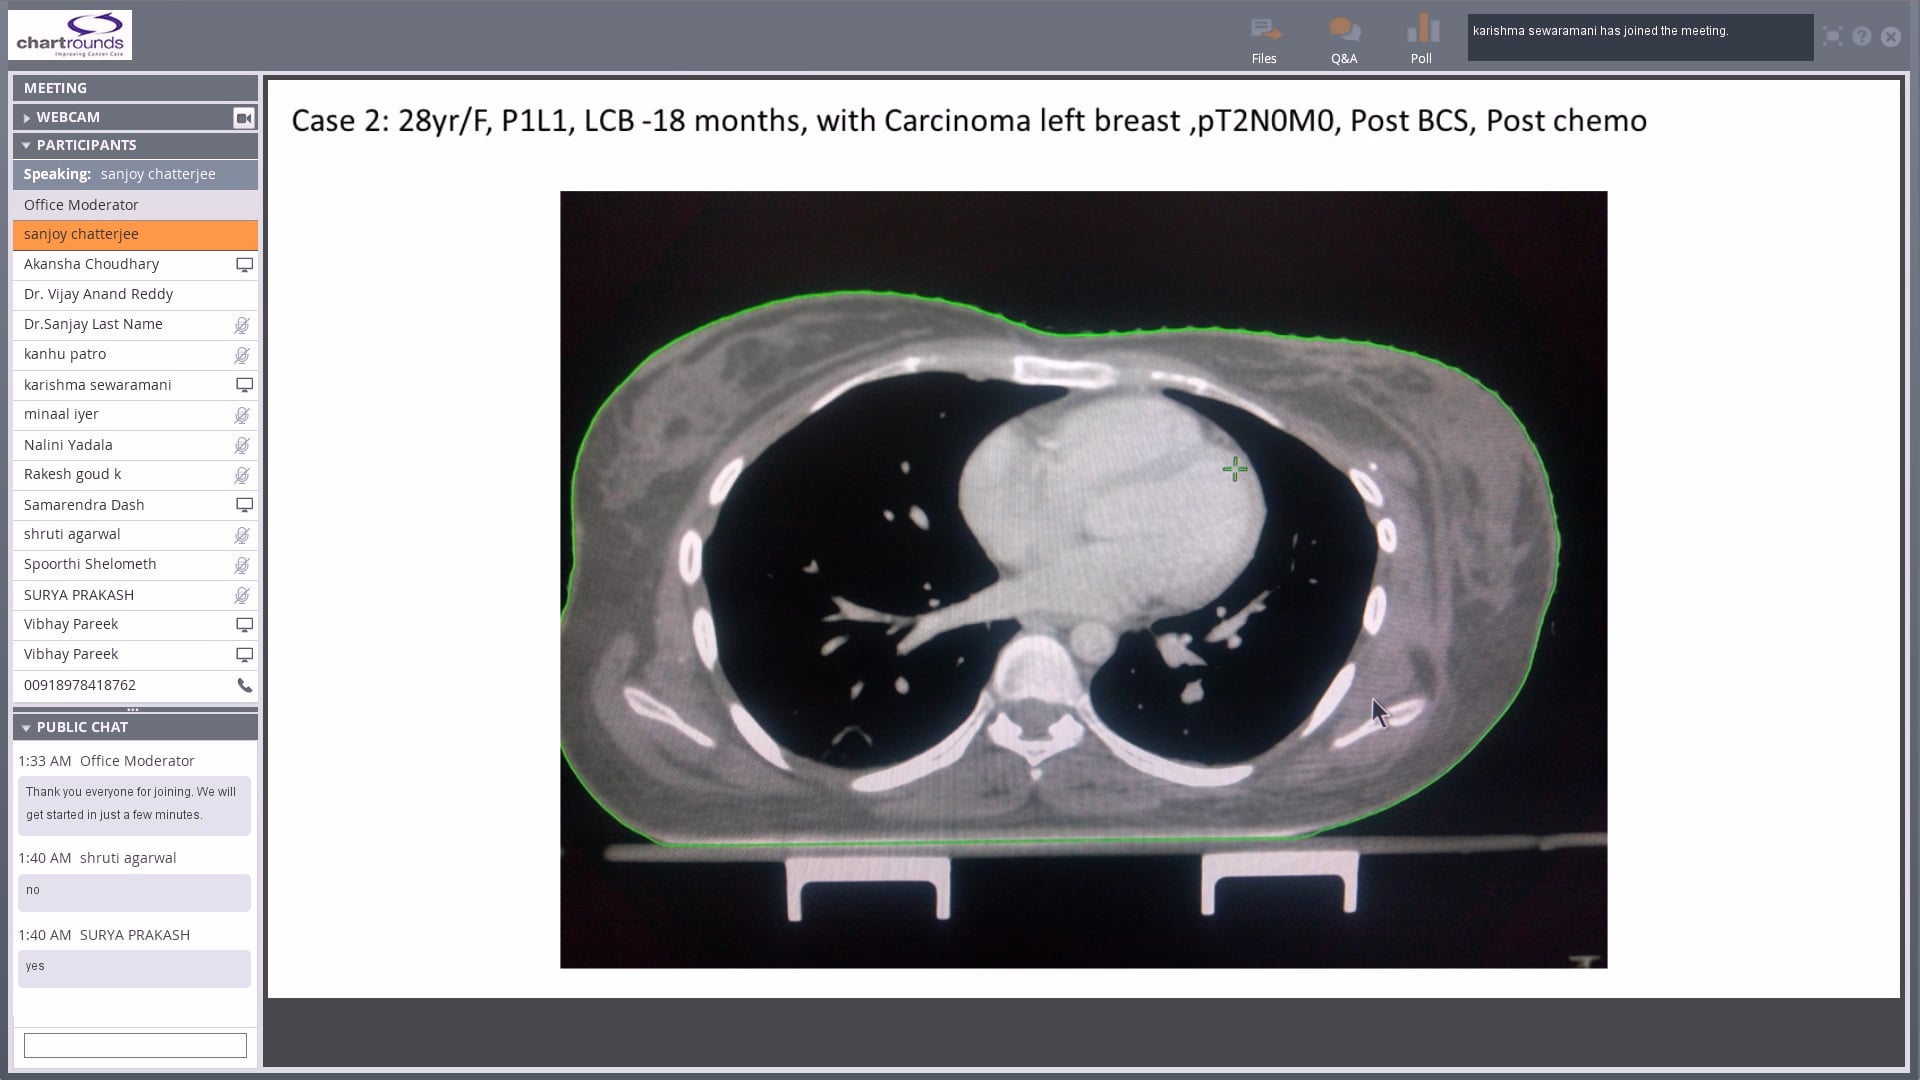

08/02/18 - Dr. Sanjoy Chatterjee - Radiation Oncology - Breast India

Invasive ductal carcinoma of the right breast post MRM, left breast carcinoma, role of adjuvant RT, the axilla and hypofractionation, IMRT